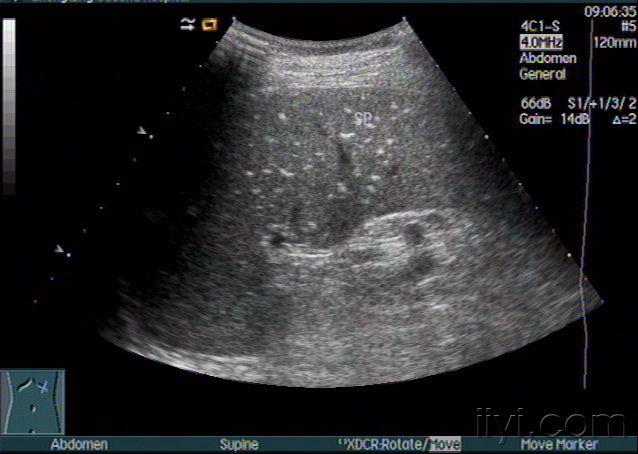

52岁,女,无肝肾囊肿,脾脏中份可见一无回声暗区.

脾脏囊肿一例 - 超声医学讨论版 - 爱爱医医学论坛

图片尺寸768x576